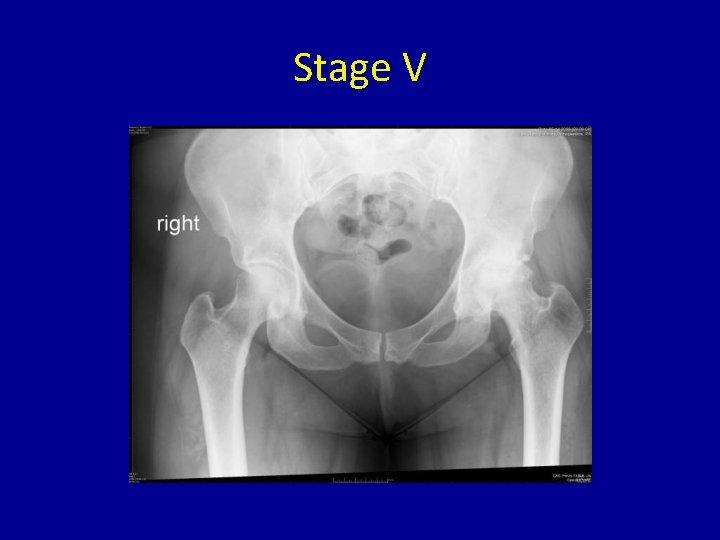

Stage V • Arthritic changes evident on x-rays with loss of joint space and spurring • May affect acetabular side of the joint

Stage V